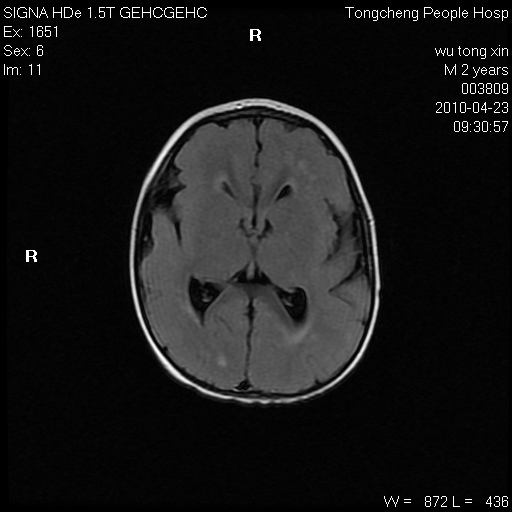

以下是引用赵物学在2010-4-25 12:43:00的发言:[br]巨脑回[br]侧脑室后角低密度影考虑hie或肾上腺脑白质营养不良?[br][br][本贴已被 赵物学 于 2010-4-25 12:51:28 修改过]

以下是引用gaoxiao在2010-4-25 16:54:00的发言:[br]巨脑回畸形。脑白质髓鞘化不良

以下是引用pujunzhi在2010-4-25 21:35:00的发言:[br]考虑 1双侧大脑皮质发育不良 2轻度脑积水 3双侧脑室后角旁片状长t1长t2信号,需继续观察,因为正常小儿此处脑白质的髓鞘化时间可以延迟到4-6岁,才显示正常。